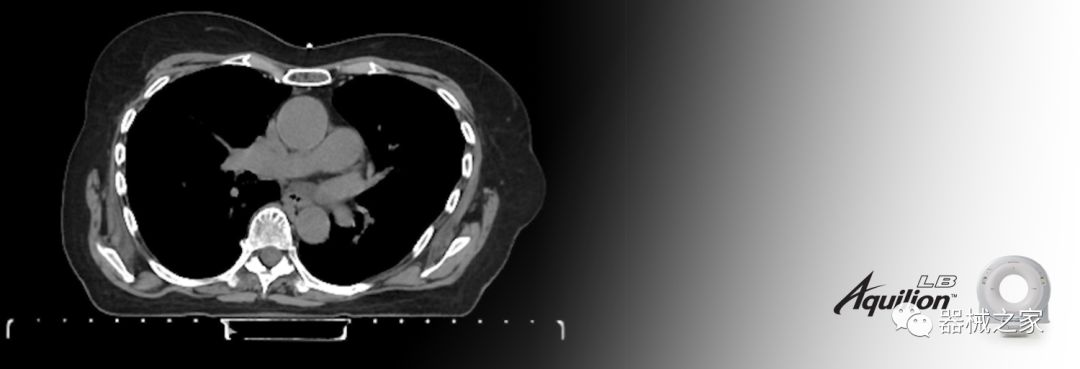

在以患者為中心的放射腫瘤學領域,計算機斷層掃描(CT)的可訪問性,可重復性和靈活性至關重要。為了建立這些價值,佳能醫(yī)療系統(tǒng)美國公司現(xiàn)在正在擴大其放射腫瘤學CT模擬產品,包括Aquilion Prime SP和Aquilion Lightning 80高級CT系統(tǒng)。除了Aquilion LB之外,Aquilion Prime SP和Aquilion Lightning 80現(xiàn)在還包括放射治療(RT)選項,可為腫瘤學規(guī)劃提供高質量的CT成像和精密工具。

擴展視野(EFOV)可以看到更多的解剖結構。Aquilion LB采用85 cm EFOV,而Aquilion Prime SP和Aquilion Lightning 70采用70 cm EFOV。

Aquilion LB專為滿足腫瘤學挑戰(zhàn)而設計,同時優(yōu)先考慮患者護理。Aquilion LB的內徑為90 cm,能夠幫助復雜的患者設置并提高患者的舒適度。CT模擬定位可以輕松鏡像放射治療定位,更加自信。該系統(tǒng)采用0.5 mm x 16排(32層)PUREViSION探測器技術,70 cm視野,AIDR 3D和SEMAR技術。